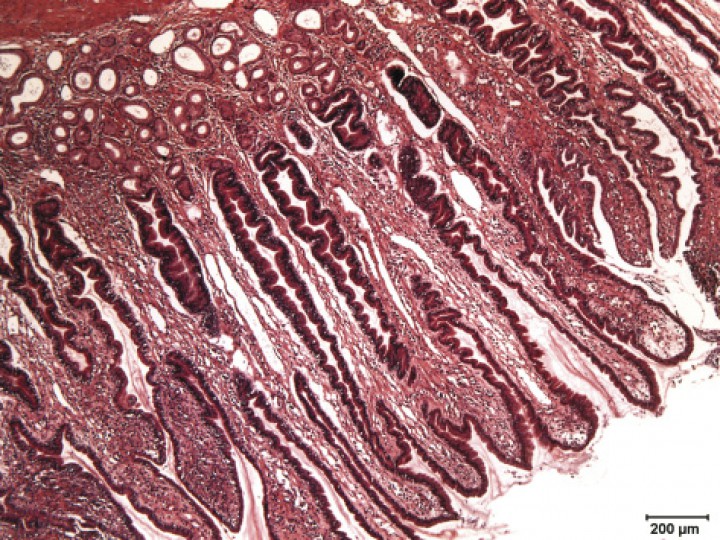

En el estudio histopatológico se observó una marcada hiperplasia del componente glandular gástrico, con presencia de un moderado infiltrado inflamatorio de tipo linfoplasmocitario (Fig. 4), siendo el diagnóstico definitivo de gastritis hipertrófica de la mucosa pilórica tipo III.

<div class=\"Basic-Text-Frame\">

<p>Imagen histopatológica de la mucosa gástrica de la zona pilórica donde se visualiza un gran desarrollo de la mucosa superficial y del cuello de las glándulas, lo que hace que las fosetas o criptas gástricas se observen más profundas. (Hematoxilina-Eosina x5).</p>

Figura 4

Imagen histopatológica de la mucosa gástrica de la zona pilórica donde se visualiza un gran desarrollo de la mucosa superficial y del cuello de las glándulas, lo que hace que las fosetas o criptas gástricas se observen más profundas. (Hematoxilina-Eosina x5).